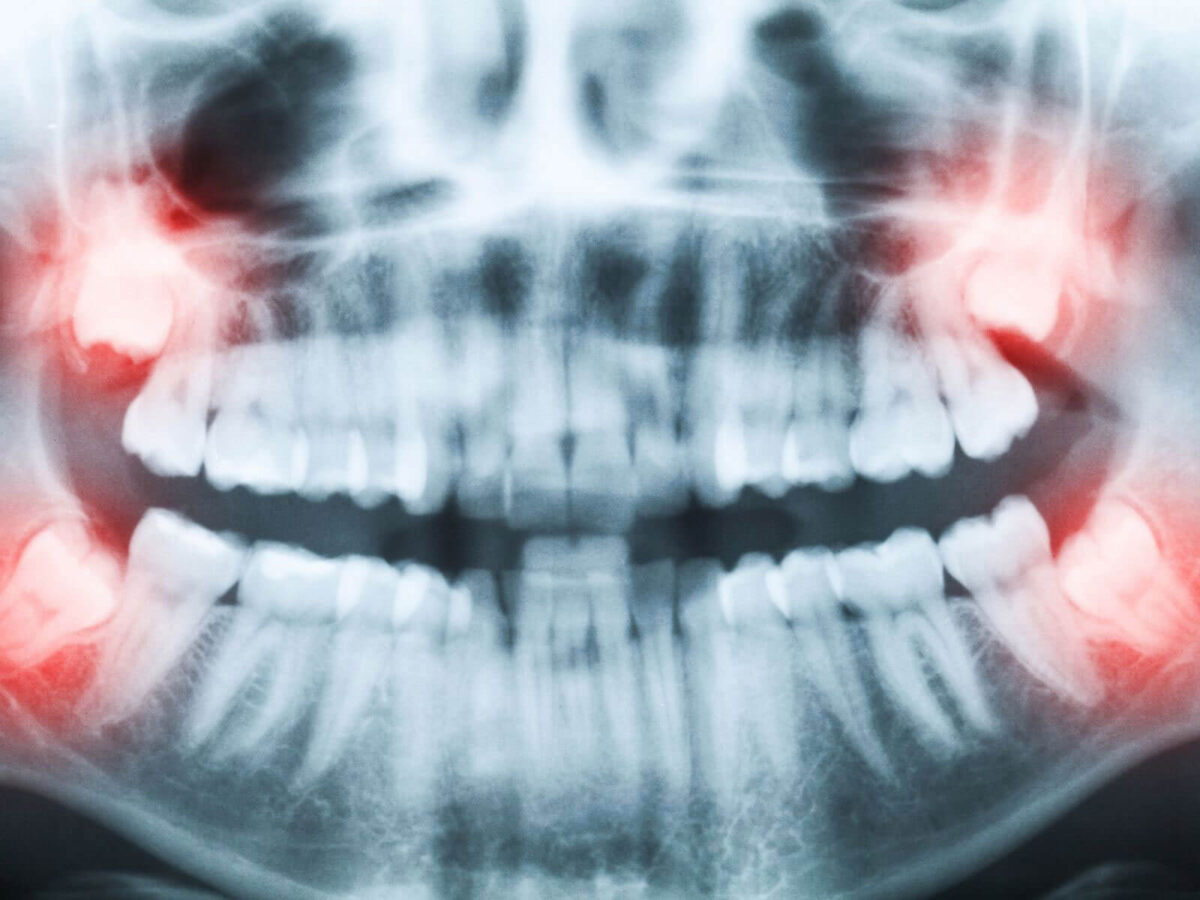

What X-Rays Reveal That The Eye Cannot See

Some of the most important findings in dentistry hide beneath the surface. A tooth may look fine in the mirror yet have decay between the sides. A gum area may appear healthy even though the bone underneath has changed. A clinician only sees these things with imaging. X-rays show the height of the bone around each tooth. They reveal early infections before swelling appears. They show whether roots are shaped normally or whether a crack might be causing sensitivity. For children, X-rays show how permanent teeth are developing and whether they have enough room. All these details guide care and reduce emergencies later.